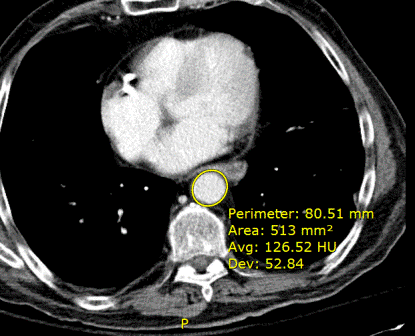

Οι πληροφορίες που εμφανίζονται μετά τη χρήση του εργαλείου μέτρησης της σήμανσης έλλειψης ROI (Περιοχή ενδιαφέροντος) μπορούν να διαμορφωθούν. Από προεπιλογή, οι τιμές περιμέτρου, περιοχής, μέσου όρου και τυπικής απόκλισης εμφανίζονται αλλά δεν εμφανίζονται η μέγιστη και η ελάχιστη τιμή. Για να το αλλάξετε αυτό, επικοινωνήστε με τον διαχειριστή του συστήματος.

Για βαθμονομημένες εικόνες, οι μετρήσεις περιμέτρου και περιοχής εμφανίζονται σε χιλιοστόμετρα (mm). Για μη βαθμονομημένες εικόνες, αυτές οι μετρήσεις εμφανίζονται σε pixel (px). Ανάλογα με τη μονάδα, οι μεσαίες, οι ελάχιστες και οι μέγιστες τιμές αναφέρονται σε HU (Μονάδες Hounsfield), GY μονάδες (Γκρι, αναπαριστά 100 Rad ή δόση της απορροφούμενης ακτινοβολίας), PV μονάδες (Τιμή Pixel) ή OD (Οπτική πυκνότητα).